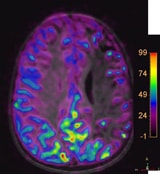

pCASL for non-contrast brain perfusion. Ingenia 3.0T.

Courtesy: Phoenix Children Hospital. Phoenix. AZ